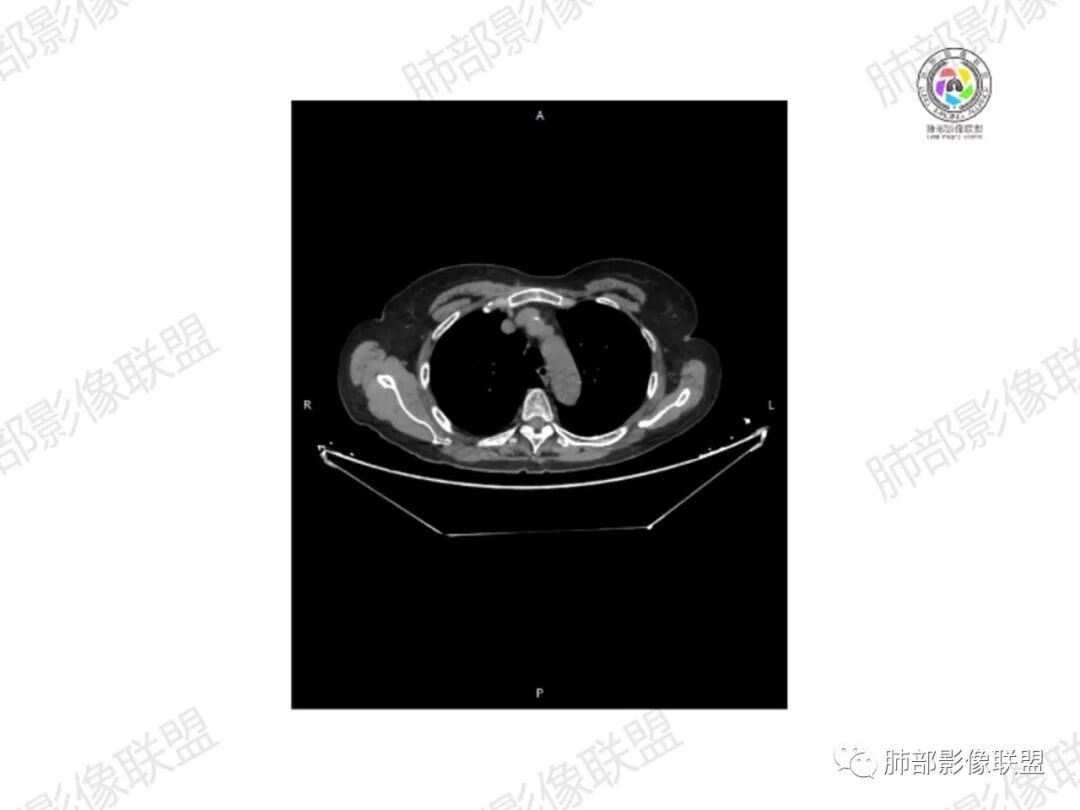

5.双肺多发类圆形结节影,边界清楚,随机分布,其间多见钙化密度影。

6.双肺门及纵隔未见肿大淋巴结。

7.扫描范围内双侧乳腺未见明显块影。

3.双肺病灶符合转移瘤,伴有中央部分钙化者也以骨肉瘤转移较为多见。